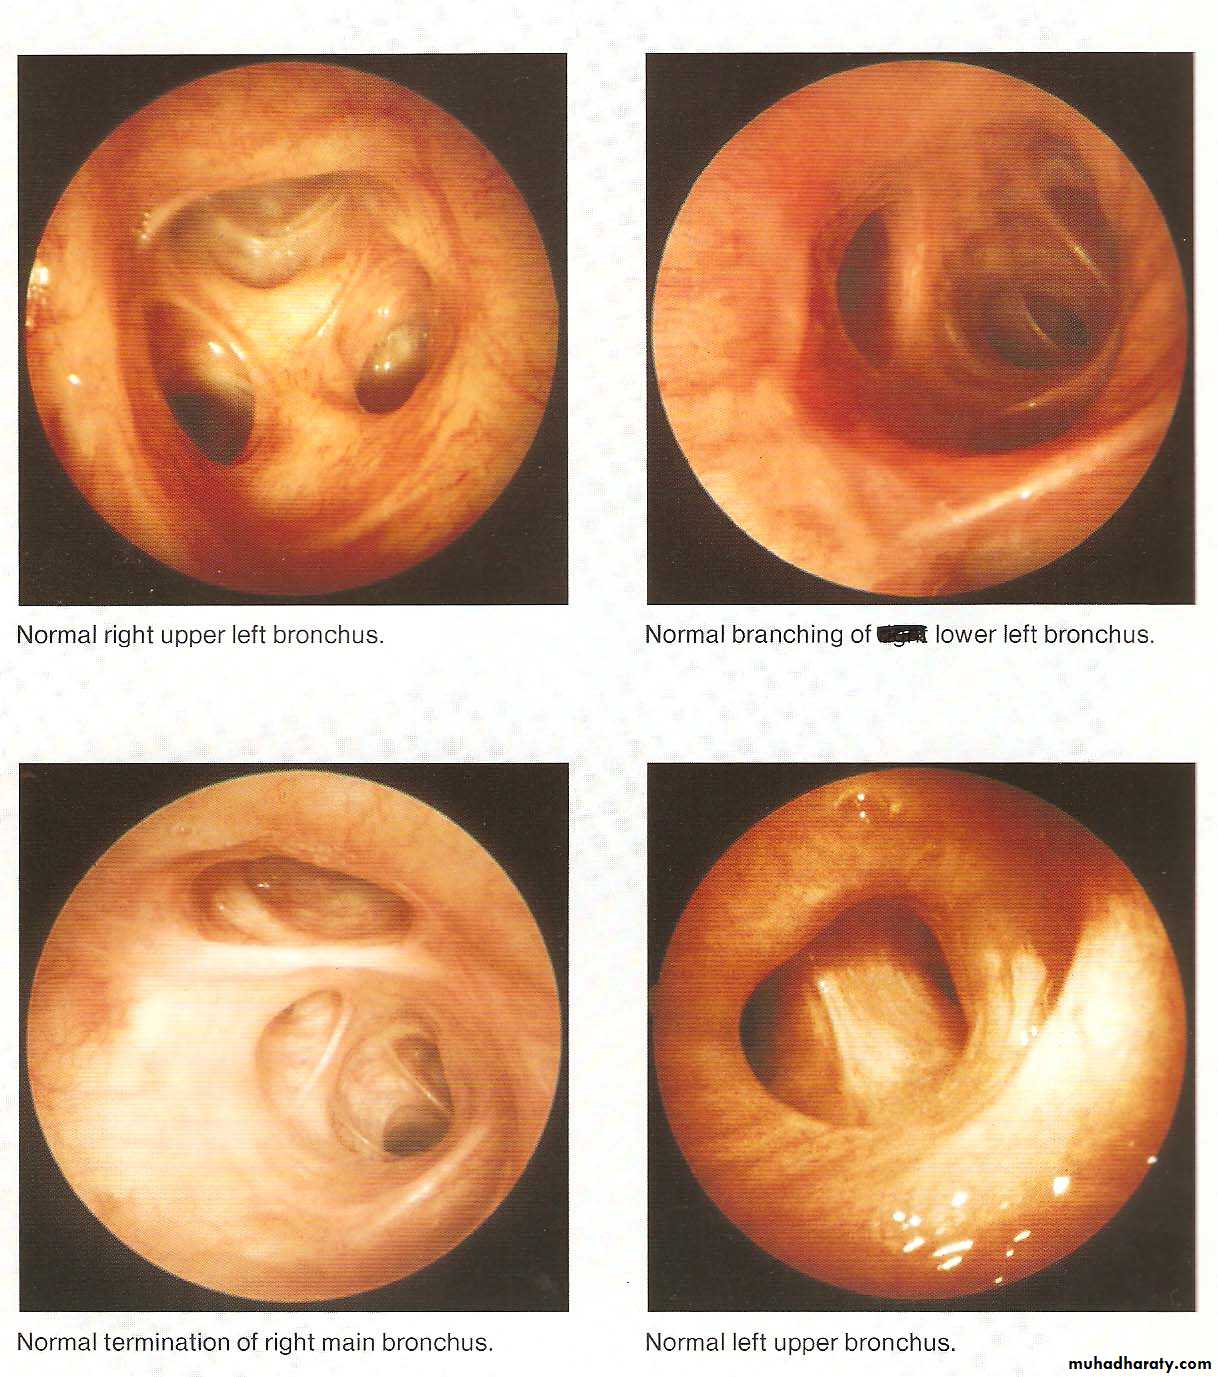

• Normal Bronchoscopic Findings

• Abnormal Bronchoscopic Findings